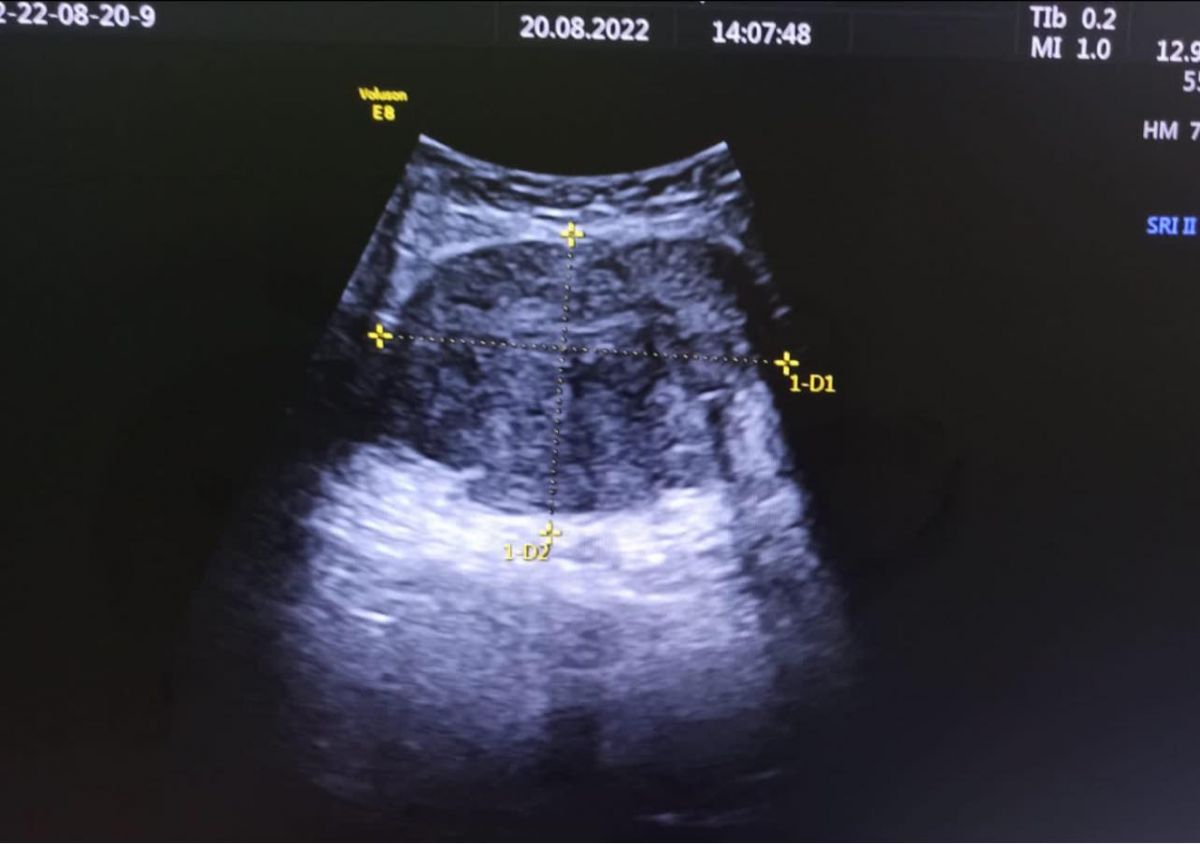

Pacienta are 54 ani și nu a declarat afecțiuni medicale în istoric. Inspecția și palparea abdominală au evidențiat o formațiune solidă, localizată suprapubian, care deforma pielea, de dimensiunea unui pumn, și durea la atingere și mărirea de volum a abdomenului în totalitate, până deasupra ombilicului, de consistență dură și sensibil la palpare.

”Ecografic am depistat o formațiune chistica cu multe septuri la nivelul ovarului drept, de aproximativ 20 cm, cu prezență de lichid liber în burtă și o altă formațiune cu caracter solid și vascularizație intensă localizată subcutanat la nivel suprapubian, de aproximativ 7 cm”,

Dr. Alexandra Ciobanu